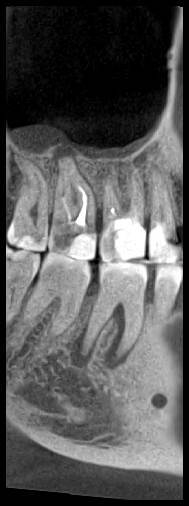

КТ от 04.03.2024

69273_3.jpg.f56a31dc1d8d53085767a9a52915128c.jpg69273_4.jpg.f9ec255bedbdb9fde8159318d3cb1fd9.jpg69273_5.jpg.36a7a942d403dd2eb062e5a4b2b58a52.jpg69273_6.jpg.492d3fbca3808fbdf58c86056b2fe0c3.jpg69273_7.jpg.f9bfdd5d593504dc7bd3710ece18aa4f.jpg69273_8.jpg.853e2342e6f2329a2e89c8939c2aad6f.jpg69273_11.jpg.e495813d50bf007f7165bf5f5dfec4b3.jpg69273_12.jpg.49b3cf66b4dd26b5cd68a91b2684e402.jpg69273_13.jpg.5d61b621b8e8b2c473ad6a8aca42502d.jpg

КТ от 28.05.2024

28_05.24(2).jpg.0ffa1febe861106733e1de830afbe6f4.jpg28_05.24-1(2).jpg.9c45d7be16aeed505bd413ce9bc6e69e.jpg28_05.24-2.jpg.a728a7d7e6213c1c8302b43adc89e4d0.jpg28_05.24-4(2).jpg.ac43f3448a3988c7006f74e1d0ce09da.jpg28_05.24-6(2).jpg.dd1fd85c6cc0fcd3d43bd9e71fc0d616.jpg28_05.24-8(2).jpg.885c8cb905445e9308f124fb9e5c616b.jpg28_05.24-9(2).jpg.6cceaaaa1b56d0967482c87b951fbe2d.jpg28.5.24-5(2).jpg.b2d79427a16769c9fd4f0d0911a9db8f.jpg28.5.24-7(2).jpg.f6c17f9820e72dc2708955a65a190b57.jpg28.0524-3(2).jpg.0aa9f153071766a340b428158a94ade8.jpg